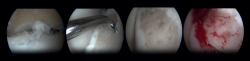

Arthroscopic Bone Marrow Stimulation (BMS) is the most frequently used treatment for primary OLT(22). BMS can be deployed for relatively smaller (<15 mm), non-cystic, non-fixable lesions(20,23). Arthroscopic BMS starts with debridement and curettage of the defective cartilage and subchondral bone(24). Subsequently, drilling or perforation of the sclerotic bone at the base of the defect is performed, often using a Kirschner wire or microfracture awl(25). The holes should be made to a depth that results in bleeding of the subchondral bone or the presence of fat droplets(23) (Figure 4). This technique disrupts the intraosseous blood vessels, leading to the subchondral bone bleeding and the formation of a fibrin clot. The release of mesenchymal blood cells promotes vascularization which induces the formation of fibrocartilage(26). When an isolated (i.e., no other damage to bone/within the joint) cartilage lesion with a macroscopically intact subchondral bone layer, is present, debridement only can be performed(27).